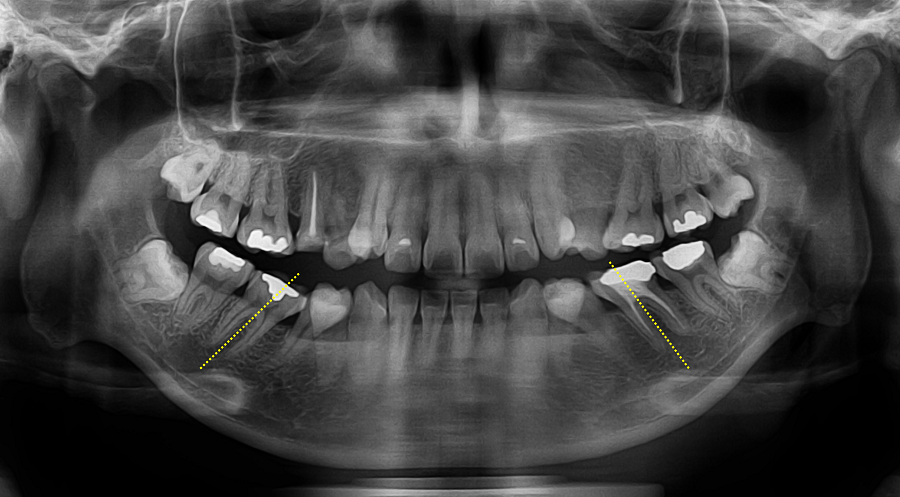

③ 미니스크류 기반 후방이동 — 이 케이스의 핵심 단계

● 상악 좌측 구치부

상악 좌측 제2소구치 결손으로 인해 전방으로 이동해 있던 대구치를 원래 자리로 후방 이동해야 견치와 전치부 공간이 회복됩니다.

대구치를 후방이동 시키기 위해 미니스크류를 식립해 안정적인 고정원으로 삼았습니다.

● 하악 양측 구치부

특히 하악은 핵심 포인트가 있습니다.

• 제2소구치가 심하게 설측 경사

• 그 공간으로 대구치가 전방으로 쓰러져 있음(tipping)

• 일반적으로 미니스크류를 가장 많이 식립하는 위치인 interradicular(치근 사이) 스크류 식립보다는

특별하게 **retromolar pad(하악 구치 후방 부위)**에 미니스크류를 식립했습니다.

이 부위에 스크류를 심으면 후방 견인과 치아의 직립에 매우 효율적입니다.